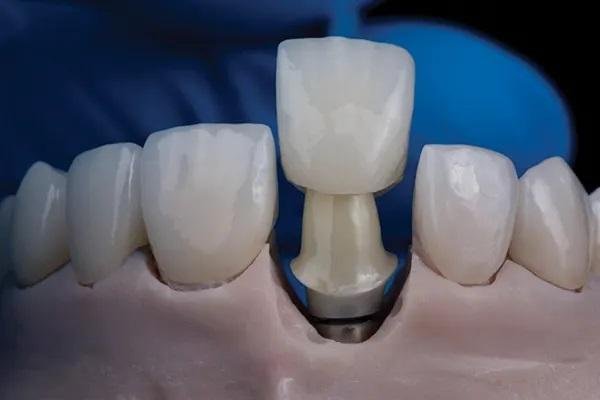

Пациентка 33 лет обратилась с жалобами на дефект прямой реставрации в переднем отделе выполненной из специальной смолы, имеющаяся у нее конструкция с опорой на имплантаты также имела дефект, а именно скол керамики по режущему краю резца и соседние зубы аномального размера (Фото 1 - Фото 3). В ее истории болезни не было выявлено противопоказаний к стоматологическому лечению. В 2015 году для восстановления целостности зубного ряда ей был установлен имплантат в области зуба 1.1., и рентгенологическое исследование показало, что имплантат хорошо сросся с костью. Глубина зондирования пародонта и тканей, окружающих имплантат, составляла от 3 до 4 мм, без признаков активного воспаления. У пациентки был хороший уровень гигиены полости рта.